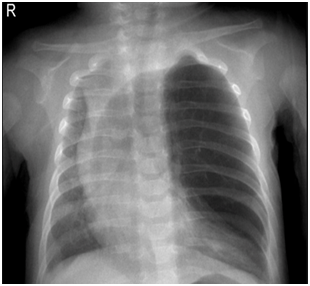

- AP Chest radiograph:

- Air in the pleural space.

- Flattening of the diaphragm on the affected side.

- Shift of the mediastinum away from the pnuemothorax (Figure 1).

Figure 1 Neonate with Right Tension Pneumothorax.